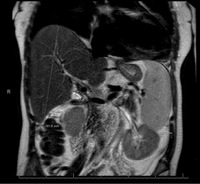

CT Abdomen Pelvis demonstrating hepatosplenomegaly consistent with cirrhosis physiology